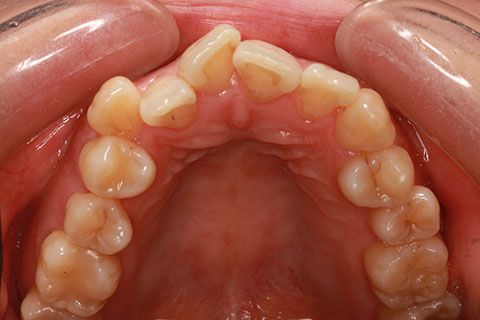

ハーフリンガル矯正3:上の歯のみ舌側矯正で治療(矯正期間24ヶ月)

治療前

治療中(開始直後)

治療中(開始半年後)

治療後

- 年齢・性別

- 25歳女性

- 治療期間

- 2年0ヶ月

- 抜歯

- 上下4番抜歯

- 治療費

- 110万円

- 備考

- 治療内容

- 施術の副作用(リスク)

- 表側矯正と比較して、力学的な操作性が複雑なため、ボーイングエフェクトを起こしやすい。